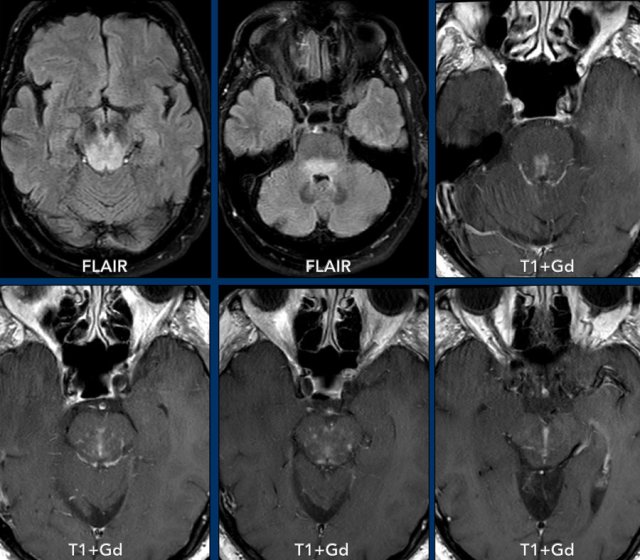

These images are of a 63-year old patient.

Images

CT shows a dense periventricular

lesion with surrounding edema.

On the T2W-image the lesion has a relatively low density. There is homogeneous enhancement of the lesion with multiple periventricular enhancing

lesions.

The density on the CT and the distribution are highly suggestive of lymphoma.

These images are of a 76-year old woman, who was confused after a fall.

First look at the images and then continue reading.

Question:

- What is the most likely diagnosis?

- Which findings are typical for this diagnosis?

The findings are:

- Hyperdense lesion on the NECT with some vasogenic edema.

- MR shows multiple lesions with solid enhancement and diffusion restriction.

- On T2W the lesions show a low signal intensity

- One lesion is located in the corpus callosum and another one is periventricular.

All these findings are typical for a primary CNS lymphoma, which is different from a systemic lymphoma.

These tumors make up for 6-7% of all CNS tumors and the histology is a B-cel NHL.

They are mostly located periventricular subependymal, in the corpus callosum and in the basal ganglia.

Always think lymphoma in a solid enhancing lesion which is located near the ventricles.

The hyperdense appearance on CT and the slight hypointensity on T2W-imaging, as well as the restricted diffusion are attributed to the dense cellularity of the lymphomatous tissue.

In immuno-compromised patients the enhancement can be ring-like.

This patient has a lot of edema, but in many cases the edema is very limited.